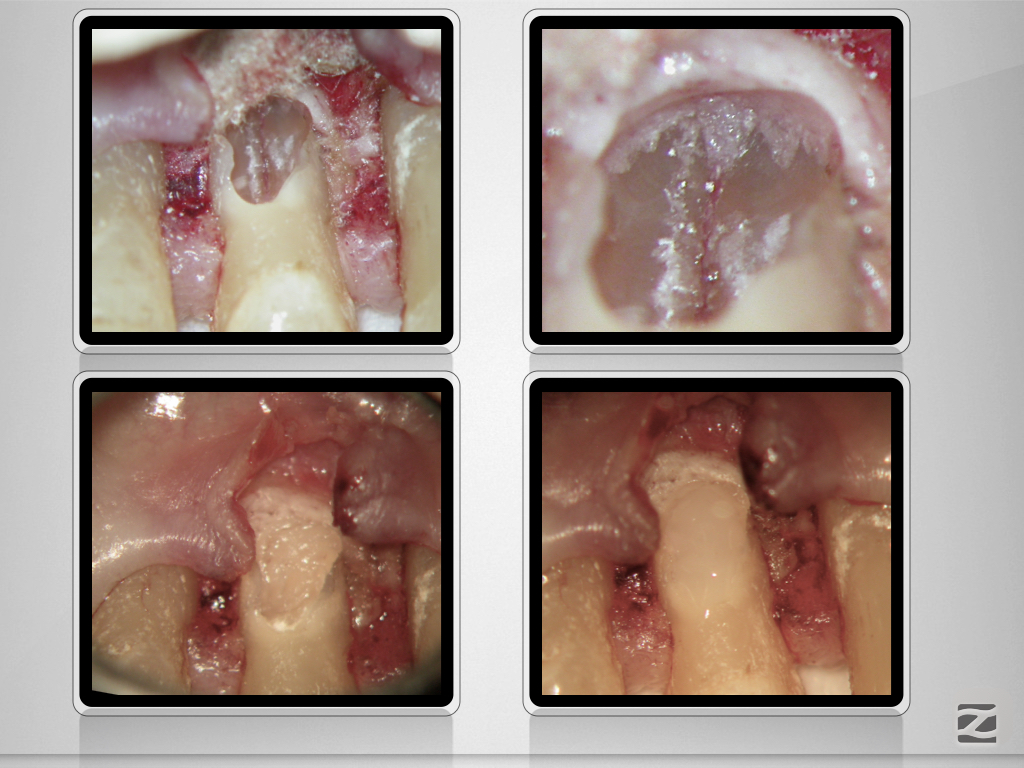

Trauma, externe Resorption & Pulpotomie